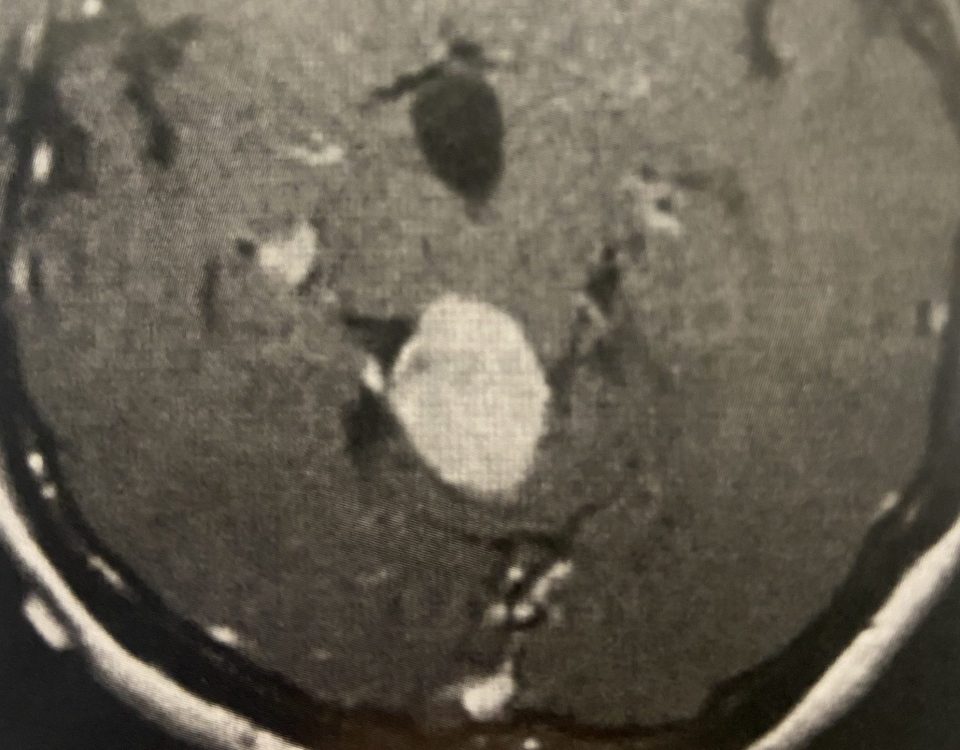

MRI with gadolinium confirmed the likely diagnosis of convexity meningioma, a benign neoplasm of the meninges. Given the location of the tumor, angiography and embolization were […]